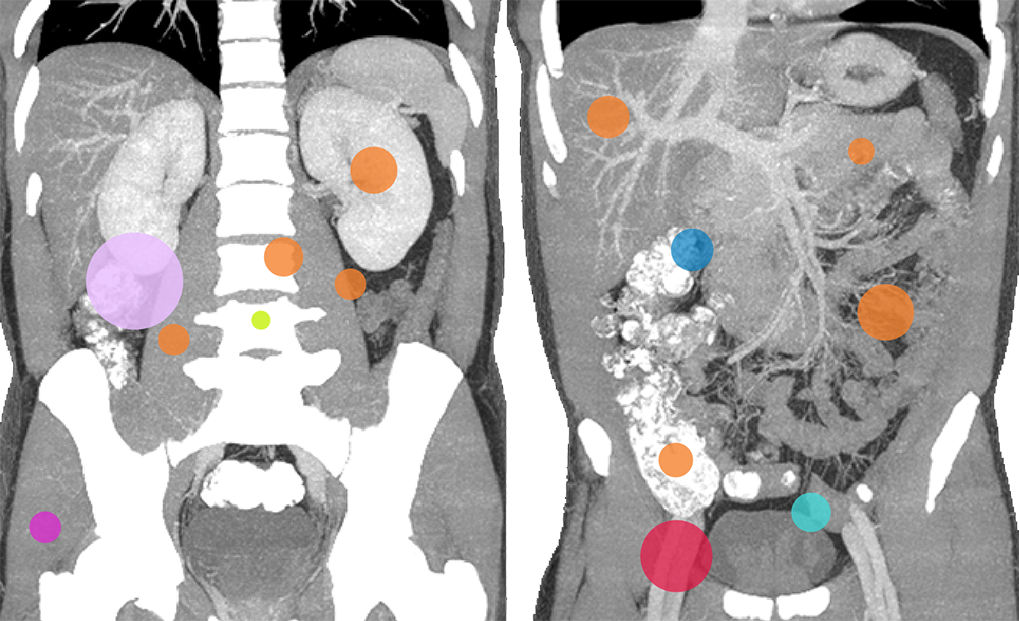

(diameter proportionate to frequency)

- Liver lesions can be subtle. Use a "Liver" window to increase sensitivity.

- Review tumor markers.

- Masses in the mesentery/peritoneum are often overlooked. Take advantage of multiplanar imaging and look in characteristic locations for peritoneal lesions.

- Kidney masses are also overlooked. Look carefully at the collecting system and for renal contour abnormalities.

- Do not forget the bones. Pay attention to endplates and cortical margins.

- Do not forget the paraspinal soft tissues. Using narrow windows to detect soft tissue abnormalities is useful.

- “Running the bowel” or tracking from above from the esophagus through the duodenal sweep and into at least the proximal jejunum and from below through the ileocecal valve into the terminal ileum is critical.

- Watch for wall edema and surrounding fatty infiltration as a sign of infection/inflammation associated with the digestive tract, especially the appendix.

- Look for filling defects in the vessels. Venous enlargement might indicate acute thrombus and confirming increased density by applying tight windows to potentially detect acute venous thrombus can be useful.

- Even without hydronephrosis, consider the possibility of ureteral calculi and attempt to follow the course of the ureters to screen for stones.

- Look carefully for small stones in the ureter/UVJ. Familiarize yourself with the normal location of the ureterovesical junctions and the configuration of the distal ureter to discriminate phleboliths from potential distal ureteral calculi